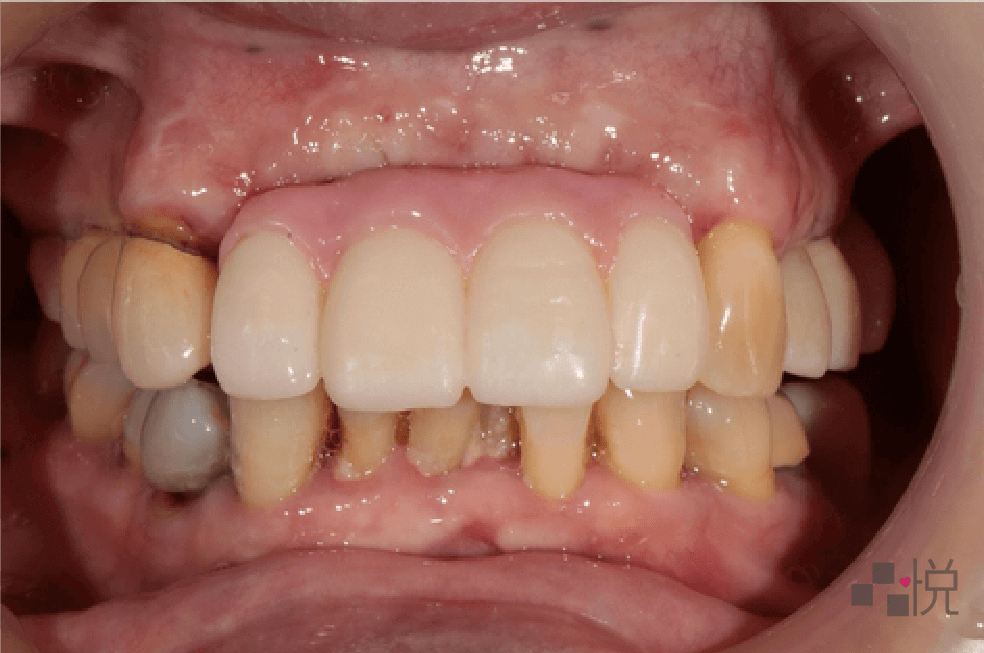

以下是從饒醫師這裡畢業的全口重建案例:

住在附近的張女士(化名)以前覺得牙齒痛了再處理就好,不過隨著年紀大,牙齒位置越來越歪,甚至會嚇到人,且不時有腫痛情形。

缺牙也讓生活品質下降、身體狀況惡化更快,於是決定來找饒醫師好好治療整理一番。

經由診斷,張女士多年的牙周病造成牙齒「病理性位移」,不只是外觀完全改變,還會發出臭味、到處不時流膿發炎。牙周病發病前期都不大會痛,發現時往往已經非常嚴重。

由於牙周問題嚴重,先由牙周醫師做全口牙周雷射治療,並拔除沒有救的牙齒。

由於長期發炎造成骨頭都被侵蝕,外觀嚴重塌陷,缺牙區採用兩階段補骨及植牙。

中間過程怕會沒有門牙、不但不美觀且無法進食,因此使用臨時活動假牙,大大提升過程中的生活品質。

由於本來的缺損太嚴重,最終假牙部分則採用陶瓷假牙肉來模擬真牙,並搭配多種不同的假牙形式,歷時一年多,終於重建進食功能及笑容,讓全院所的醫護都相當欣慰。